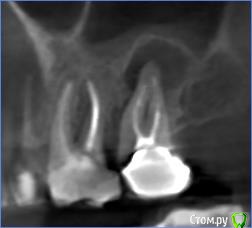

anafree Опубликовано 25 февраля, 2016 Поделиться Опубликовано 25 февраля, 2016 (изменено) Добрый вечер! Подскажите, пожалуйста, возможно ли попробовать перелечить, удалить кисты без удаления зубов? То что дорого, знаю. Интересует, есть ли возможность вообще в данной ситуации. Две верхние семерки, там стоят вкладки и коронки (стоят уже лет 10) и нижняя 7-ка, там пока временная коронка на штифте просто стоит. Ни один из трех зубов не беспокоит. Изменено 25 февраля, 2016 пользователем anafree Ссылка на комментарий

DmitrySH Опубликовано 26 февраля, 2016 Поделиться Опубликовано 26 февраля, 2016 Да, можно спасти, но возможно что не все, для полноценного ответа нужно больше снимков. И то, на снимках всего не видно. Чем качественнее сделаны вкладки, тем сложнее их извлекать. Ссылка на комментарий